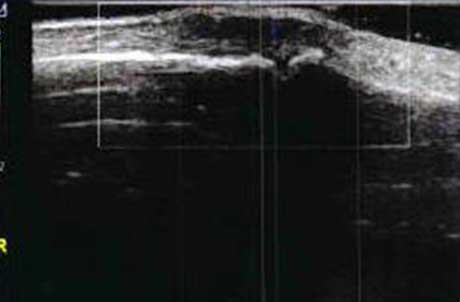

1、动态观察滑膜血流信号,早期监测RA活动

肌骨超声血流成像可清晰反映滑膜的血流情况,观测滑膜周边及内部异常血流信号的增多、血管翳增生程度,以及呈现出点状、星点状或枝状的不同形态,做到在RA的早期发现异常图像变化。通过对图像中血流信号的多少及区域范围进行评分,以此来辅助判断RA的活动程度。